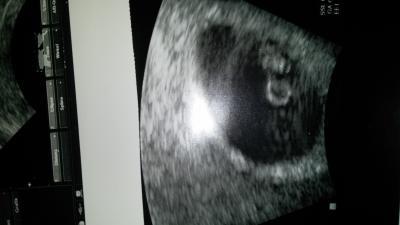

Hey Ihr lieben Mamis, wue geht es euch soweit?Mir ist den ganzen Tag kotzübel.... Hab Vomex bekommen aber es hilft net .... naja... Aber auch was gutes... heute hatt ich fast keine Blutung mehr. Das Progestan scheint zu wirken... ich ruhe mich aber auch viel aus und meine Chefin möchte jetzt für mich ein Berufsverbot erwirken weils für beide Patein erstmal besser ist.Ärzte machen das net mehr so einfach... da muss man schon bald nach der FG greifen können... Naja... ich wollt euch auch ein paar neue Bilder zeigen von unserem Krümel... Am Monat sehe ich Ihn dann wieder

huhu... tolles Bild von deinen Krümel